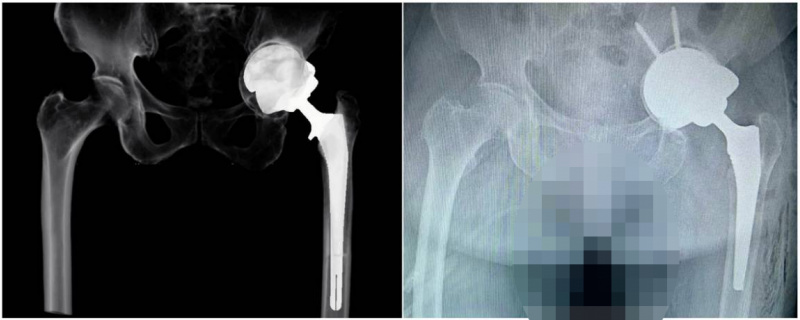

图中所示人工智能术前规划和测量软件模拟的术后X线片与真实的术后X线片相一致。

烟台市民肖阿姨8年前做过一次全髋关节置换手术,近两年出现了手术后假体松动、失效,相关检查显示:其髋臼杯松动、移位,髋臼窝有着较大范围的骨缺损,若再做假体的翻新手术,难度极大。东院关节外科团队与医学3D打印创新研究中心进行了充分沟通,打印出患者的病损侧骨盆与髋臼模型;借助人工智能技术软件进行三维空间的测量、术前假体的个性化选择和安装位置的精准规划。术中,医生根据实际情况选择了预先制定的“Cup-in-Cup”技术重建方案,在完美地填补髋臼骨缺损的同时重建新的髋臼杯,复位关节,患者重新获得了符合其生物力学特点、翻新的人工髋关节。